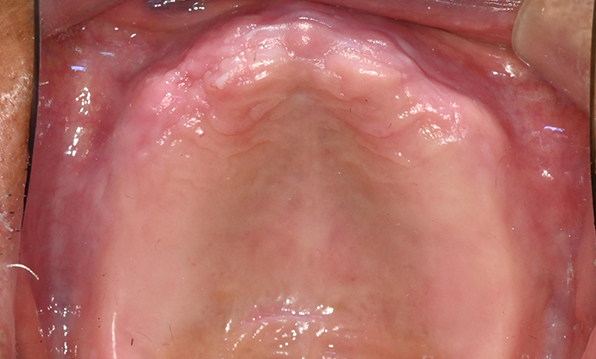

Before & After

Case 03

Before After

Case 04